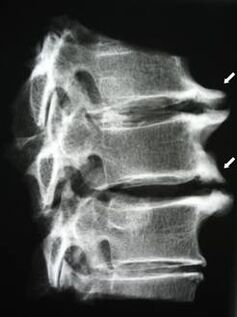

In the early stages, osteochondrosis is detected by MRI.Later, the pathology can be diagnosed using radiography.On x-rays of the cervical spine, a decrease in the distance between the vertebrae, pathological changes in the facet joints and osteophytosis become noticeable.

| Cervical osteochondrosis | The appearance of pathological changes in one or more motion segments of the spine.Impaired spinal mobility, development of myofascial pain syndromes and spinal root compression | Pain, paresthesia and motor disturbances in the cervical region, which spread to the back of the neck and upper limbs.Detection of characteristic changes in the spine on MRI and x-rays (osteophytes, decreased distance between vertebrae, signs of damage to intervertebral joints) |